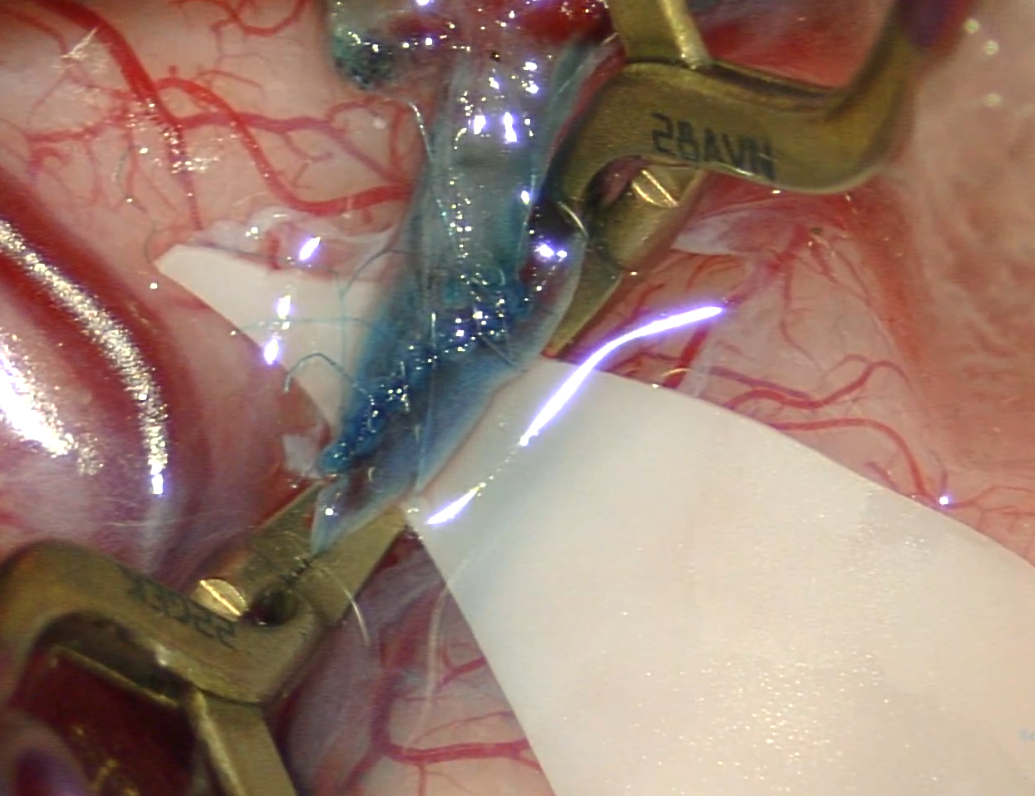

打开硬膜以后,发现脑皮层动脉萎缩变细:

基本都达不到1mm。

最后在脑沟里翻出一根稍粗点的血管,但是一端扎入更深处,一端马上分叉,能利用的范围很小:

缝合空间有限: